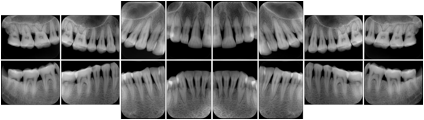

- OO-1. Intra-oral Full Mouth Series Structured Display